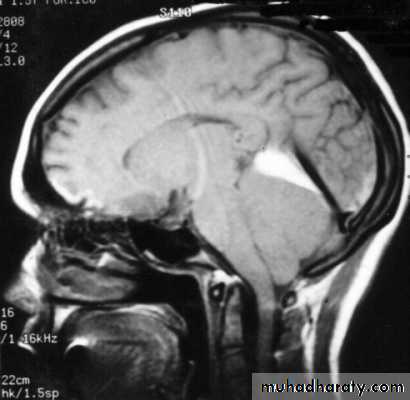

CT scan: the acute clotted blood is initially appears white (hyperdence), but as it liquefies, it slowly becomes black (hypodense).

They should be drained if they continue to enlarge.

They are evacuated by drilling burrholes over the collection and washing it out with warmed saline.

Chronic Subdural Haematoma